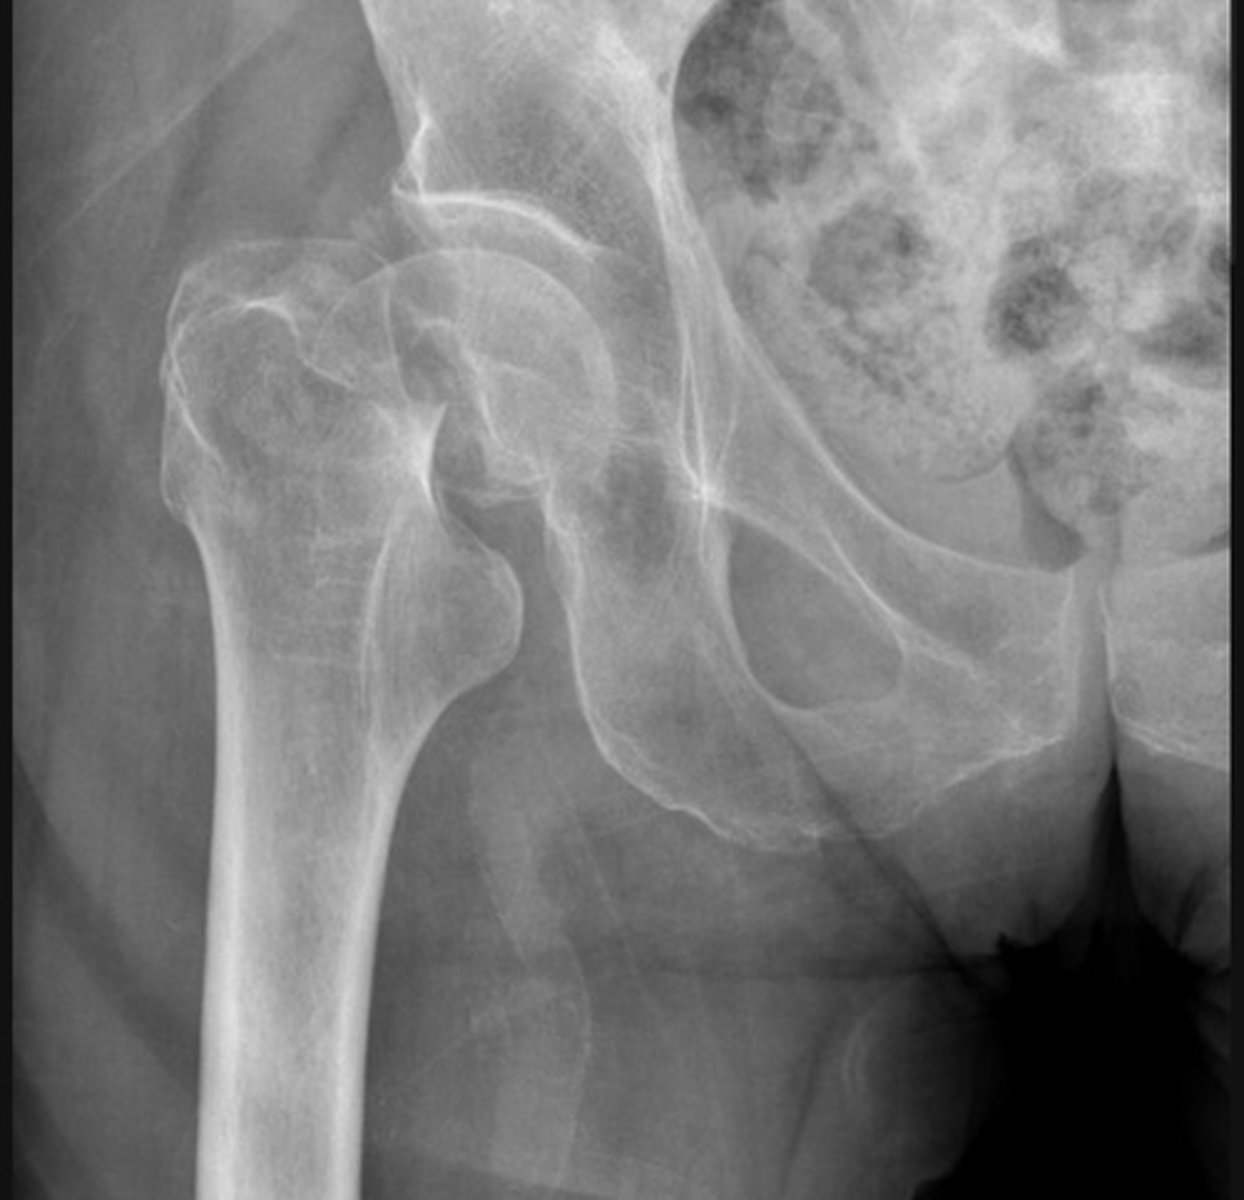

Subcapital fracture with complete displacement

Transcervical fracture with minor displacement

Subtrochanteric fracture

The bone texture is abnormal in this patient with a known malignancy - indicating a pathological fracture

A fracture of the femoral neck is accompanied by avulsion of the greater trochanter